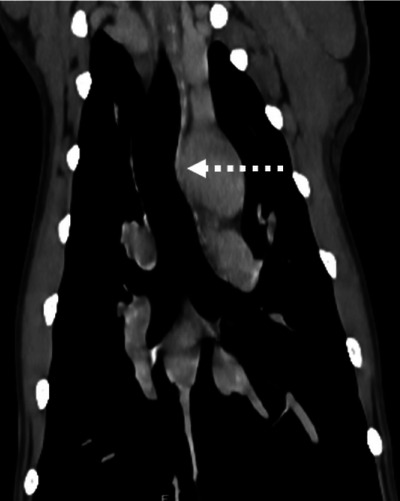

Aberrant right subclavian arteries (ARSAs) are a form of vascular ring anomaly (VRA) in dogs and the most common VRA in people. To date, there has been no large-scale study on ARSA in dogs and their potential clinical significance. For part one, a single-center retrospective observational study was performed to determine the prevalence of ARSAs in a population of 1000 dogs undergoing contrast-enhanced CT for various reasons. For part two, further canine ARSA cases were collected to characterize their imaging features further and determine whether any imaging findings were more frequent in dogs with clinical signs attributed to a VRA. The prevalence of ARSA was 1.2% (12/1000). For part two, out of a total of 37 dogs with ARSA, this finding was thought to be incidental in 28 cases (75.6%), clinically relevant in 1 case (2.7%), and potentially relevant in 8 cases (21.6%). Cranial esophageal dilation with gas and fluid and esophageal compression at the site of the ARSA crossing the esophagus was found in the case where the ARSA was considered relevant. Esophageal dilation with esophageal compression by the ARSA was also more frequent in the potentially relevant group. Our study shows that an ARSA is more likely to be an incidental finding; however, due to the low number of cases where the ARSA was considered relevant, no specific imaging findings were found that could help determine their clinical relevance.